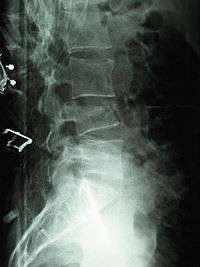

X-ray of the lumbar spine with a compression fracture of the third lumbar vertebra.